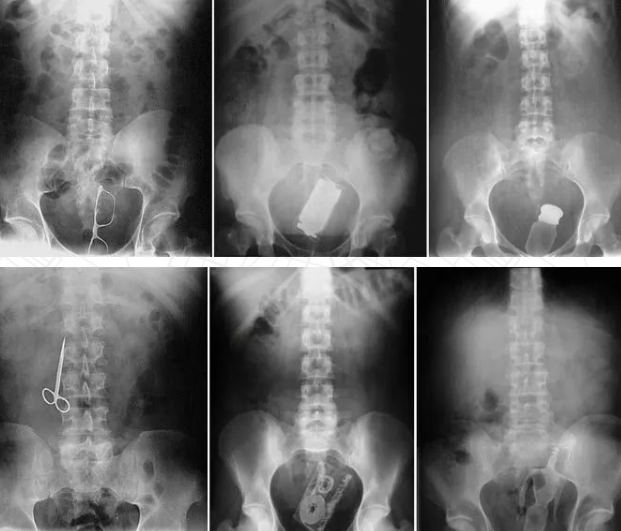

比如

所以现在基基真诚给大家百科